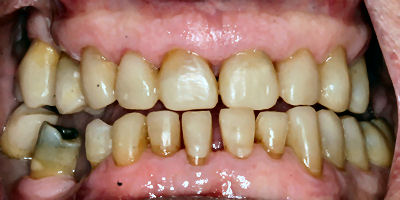

If your bite has collapsed, or if your existing teeth need modification (closing spaces or shape) then composite restorations may be suitable for you.

If only your front teeth have worn because of grinding or erosion, then we may need to correct your bite at the front only. After placement of the composite it may feel as if you have too much tooth structure. A limited number of people have noted tenderness in their jaw joint following increases in the level of their bite. Most people successfully tolerate a moderate increase in their bite especially if their bite has closed over time due to loss of tooth structure.